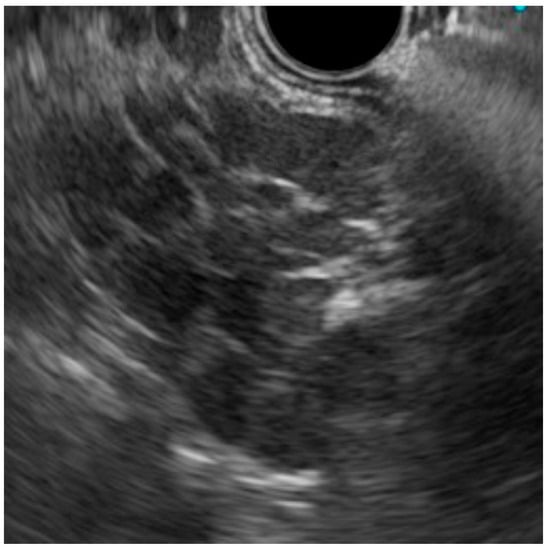

| EUS | endoscopic ultrasonography |

2. Case Presentation